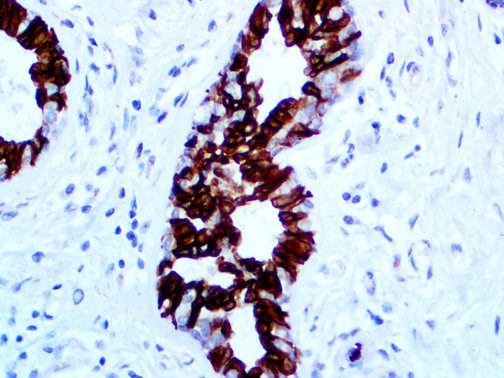

It is the ICU physician who is most likely to witness one of the deadliest manifestations of the abnormal immunological response, the cytokine storm syndrome (CSS). This response is also referred to by some as the cytokine release syndrome (CRS). CSS is characterized by continuous activation and expansion of macrophage and lymphocyte populations, which secrete large amounts of cytokines, causing the cytokine storm. This massive cytokine release is akin to hemophagocytic lymphohistiocytosis (HLH) disease, a syndrome characterized by initial unchecked and persistent activation of cytotoxic T lymphocytes and NK cells.

This activation induces inflammatory monocytes to highly express IL-6, starting a localized and then systemic cascade effect that results in hyperproduction of IL-6, which accelerates the inflammatory process. Because IL-6 also increases vascular permeability, excessive levels cause blood vessels to become very leaky. This, along with clotting factors released from vascular endothelial cells, stimulates the coagulation cascade, resulting in microthrombosis (tiny clots), which leads to ischemia and tissue death of the kidney, intestines, heart, liver, brain and extremities.